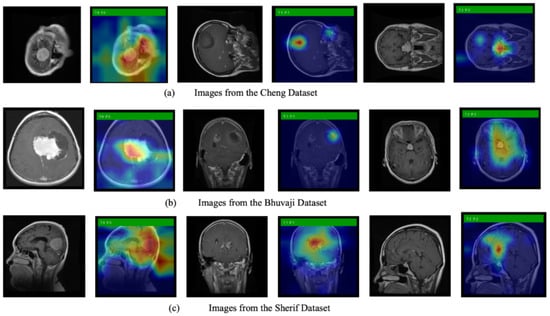

3.4. Grad-CAM Simulations

We also use Grad-CAM, an explainable AI technique, to show the model’s decision-making process. Figure 6 displays the original images alongside heatmaps overlaid on them. The regions shown in red represent the primary focus of the model. The first row of images is from the Cheng dataset, the second row from the Bhuvaji dataset, and the third row from the Sherif dataset. It is clear that in all cases, the models prominently focus on the tumor region, which enhances the trustworthiness of the model’s decisions.

Figure 6.

Original MRI images along with images overlayed with the heatmap generated using Grad-CAM.

Explainability analyses using Grad-CAM revealed that both the baseline and compressed models consistently focused on tumor regions across the Cheng, Bhuvaji, and Sherif datasets. This alignment between model attention and clinically relevant regions enhances trust in the decision-making process and underscores the suitability of ANSA-based architectures for medical applications.